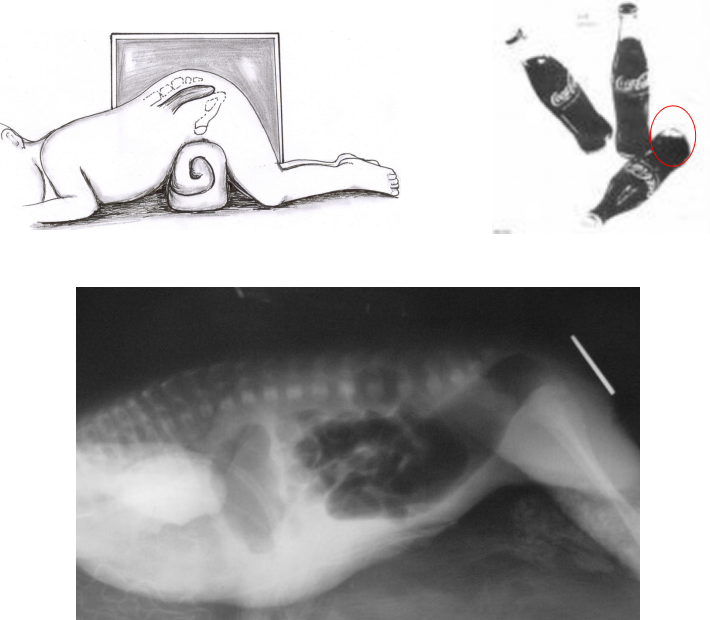

X线征象:出生12h后进行倒立侧位摄片(时间、体位、按摩、肛门标志)

▷ 高位及中位

- 结肠造瘘生后

- 6~12月 根治术

▷ 低位

- 后矢状入路肛门直肠成形术(PSARP)